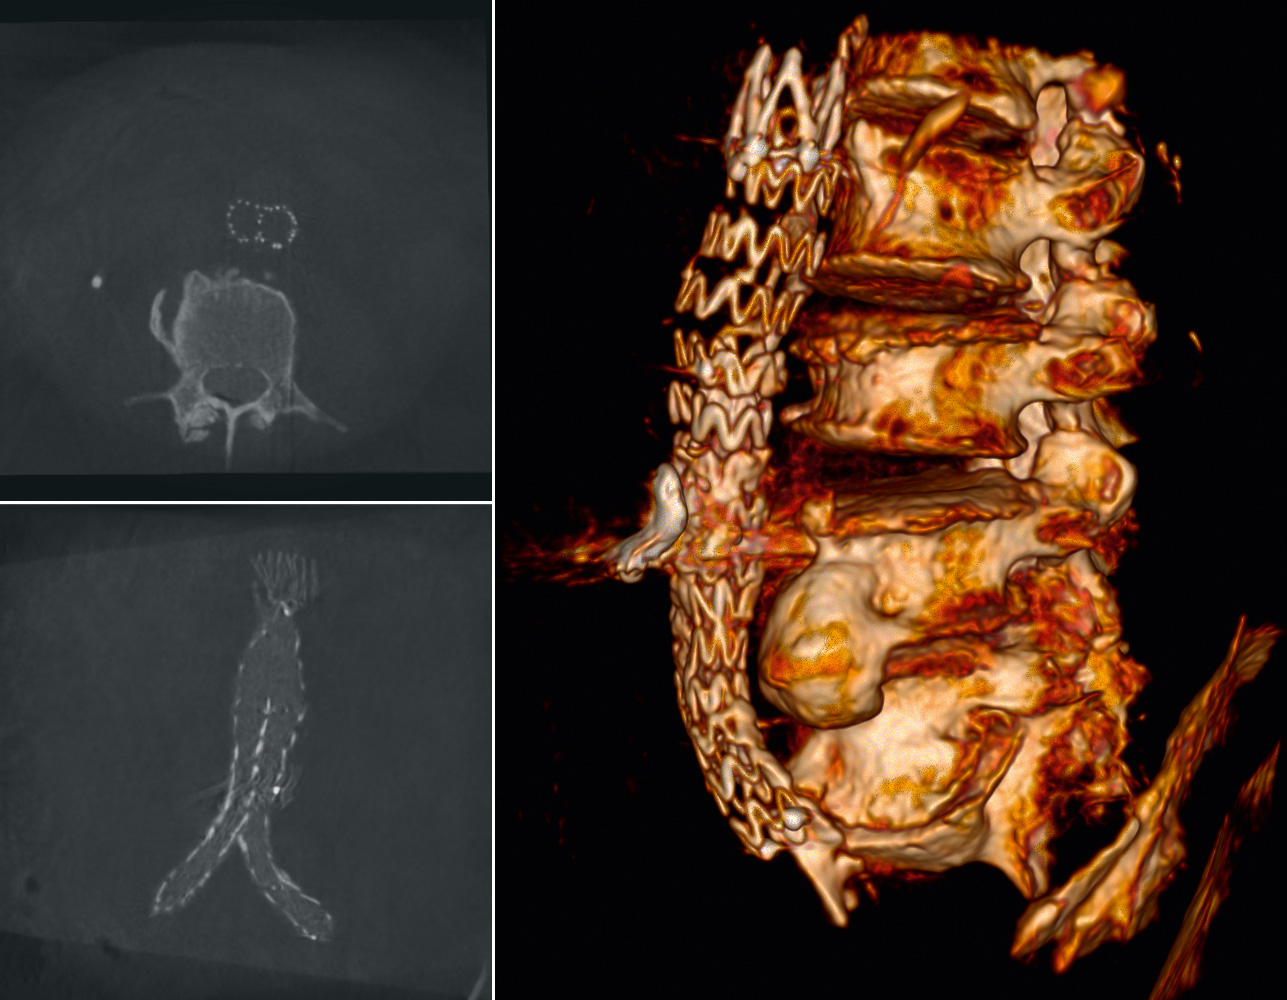

Les meilleures images cliniques du Ziehm Vision RFD 3D

Enhanced Vessel Visualisation (EVV)

Reconnaissance automatisée des vaisseaux lors d’interventions vasculaires

Fusion d’images en 3D avec Therenva EndoNaut

Système de navigation peropératoire avec fusion d’images pour optimiser les interventions endovasculaires